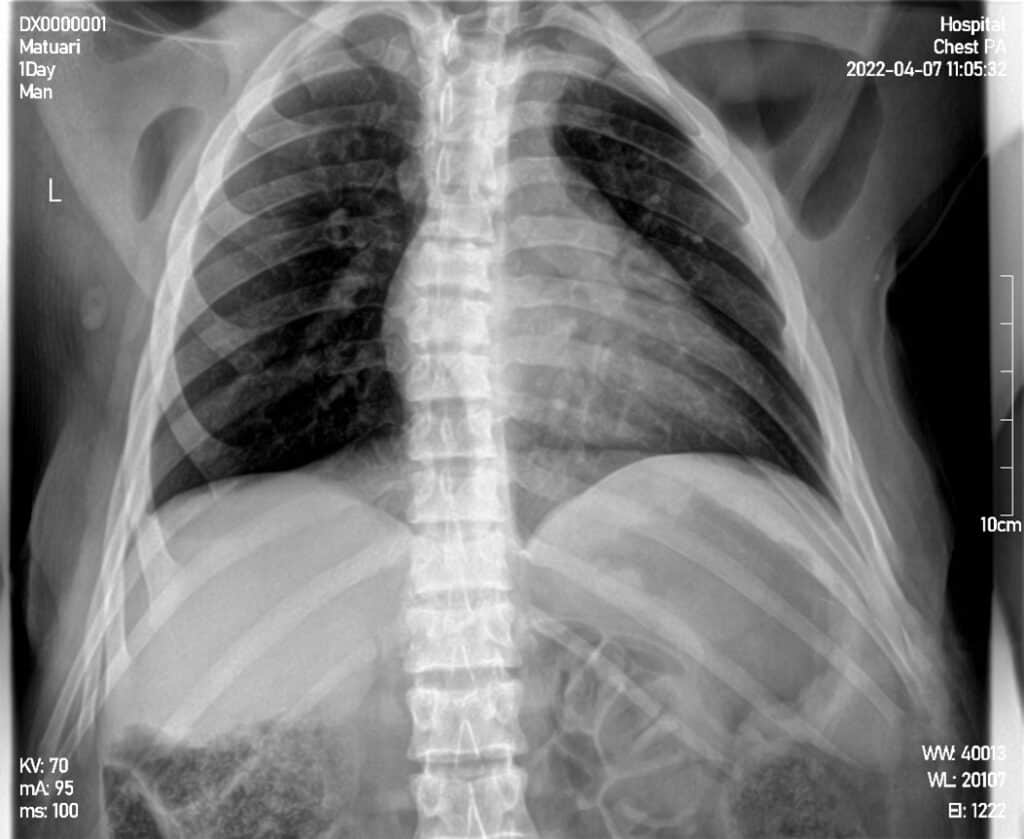

Once the machine was finally installed and the exposure capacity was fixed, SOC was able to carry out its first X-ray on an adult male orangutan named Matuari. Matuari, who is one of the largest orangutans at the Jerora Forest School (78 kg), was X-rayed for his chest/thorax and left arm. The chest/thorax X-ray was unsuccessful due to Maturai’s size, but the X-ray on the arm came back clear, leading the team to believe that the machine is best used for orangutans weighing under 75 kg.